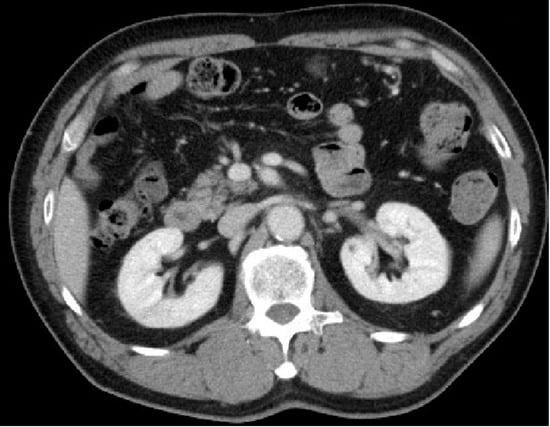

Asymptomatic Idiopathic Renal Infarction Detected Incidentally on Contrast-Enhanced Computed Tomography: A Case Report

2. Case Presentation